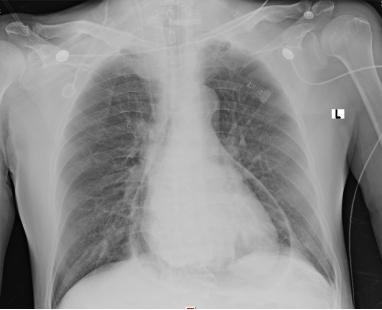

1 资料与方法患者男性,70岁,因“胸闷3 d,加重伴呼吸困难1 d”于2019年9月13日入外院。患者3 d前无明显诱因出现胸闷,伴全身乏力,夜间睡眠差(可平卧),初未予重视,1 d前胸闷加重,伴呼吸困难、运动耐量明显下降、大汗淋漓、皮肤湿冷,至外院就诊,查心电图(图 1):交界性逸搏,肢体导联低电压,Ⅰ、Ⅱ、Ⅲ、aVF、V4、V5、V6导联ST段抬高0.15 mV~0.4 mV,aVR、aVL、V1导联ST段压低0.05 mV~0.2 mV,aVL、V1导联T波倒置;心肌酶:CKMB 27.1 U/L,NT-proBNP 3 298 pg/mL。外院考虑不排除急性心肌梗死导致的心源性休克,经口气管插管接呼吸机辅助通气后为进一步诊治转入本院。患者家属否认患者有外科手术、外伤、气胸及哮喘发作史,起病以来无畏寒、高热,大、小便正常,既往1年余前因“反复咳嗽伴咳血丝痰”在外院诊断为右肺门鳞癌,合并高血压病、2型糖尿病,经依托泊苷+顺铂化疗,具体剂量不详。2019-09-07复查胸部CT提示右肺病灶较前缩小。体格检查:体温35ºC,血压86/43 mmHg,心率53次/min,呼吸15次/min(经口气管插管呼吸机辅助呼吸),神志昏迷,双侧颈静脉怒张,气管居中,桶状胸,胸廓对称,双肺呼吸动度对称,叩诊呈清音,听诊呼吸音清,双肺未闻及干湿性啰音,心前区无隆起,叩诊心界消失,心音低弱遥远,桡动脉、股动脉搏动可触及。入院后复查心电图(图 2):心房颤动,肢体导联及胸导联低电压,各导联ST-T改变较前相似,未见明显动态演变。血常规:白细胞1.27×109/L,中性粒细胞1.15×109/L,血红蛋白98 g/L,降钙素原43.01 ng/mL,超敏肌钙蛋白Ⅰ 0.048 ng/mL。急诊冠脉造影(图 3):左前降支近段轻度狭窄,中段心肌桥,收缩期重度狭窄,左回旋支远段中度狭窄,右冠中段重度狭窄,TIMI血流均为3级。患者超敏肌钙蛋白I未见明显升高,冠脉血流通畅,排除急性心肌梗死引起的ST段抬高。心脏彩超:气体干扰较大,仅能从剑突下观察,心包腔内未见积液。胸片(图 4):纵隔内可见条状透亮带,心影周围可见一弧形透亮带,考虑心包积气、纵隔气肿。入院诊断为“①心包积气、②纵隔气肿、③右肺鳞癌”,经剑突下途径行心包穿刺置管术+闭式引流术,术后液封瓶内见气体逸出,患者血压较前逐渐上升。完善胸部CT(图 5):右侧肺门增大,右主支气管与上叶支气管壁交界处见小缺损,考虑支气管破裂,心包、纵隔、胸腔及腹腔积气。纤维支气管镜(图 6)检查:可见右主支气管距隆突约1 cm处见破损,破损处周围组织呈白色,不排除癌组织浸润可能。病因考虑为右肺门鳞癌浸润右主支气管,穿孔后经纵隔与心包腔形成瘘道,引起心包积气。经过上述治疗后患者血流动力学稳定。

| 图 4 胸部正位片提示纵隔积气,心包积气 |